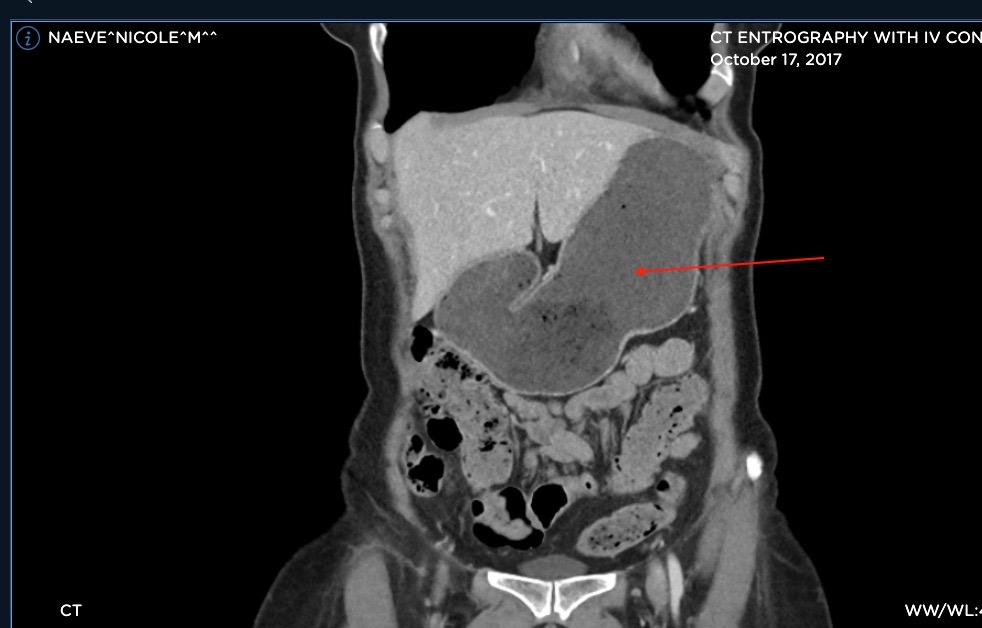

Dr. Chauhan, who I saw yesterday, looked at my most recent CT scan and had a couple observations. First, “Oh, that’s definitely MALS, look at that, it’s so obvious, there’s this huge glob of tissue sitting right there on the artery; that’s not normal!” Pointing to a fluffy white blob of which looks like all the other fluffy white blobs on the screen to me. No surprise, no one else except Scholbach has suspected this.

Second, (and this is where I think I might give myself a tiny little victory lap,) he compared my duodenum from a CT in 2017 to last weeks. “Look at this, it’s much more normal now – did you gain weight?” Yes, yes I did. My duodenum, which in 2017 took up a huuuuge portion of my upper right quadrant, (probably because it was pinched off further downstream at the SMA,) now appears about the size of one of my hands. Normal! It seems I may have successfully regained the fat pad which supports the SMA angle, which can pinch the duodenum when it’s too tight. Now, perhaps, I may enjoy a less painful digestive process.

Arrow points to duodenum in 2017:

Below, arrow points to duodenum in 2022